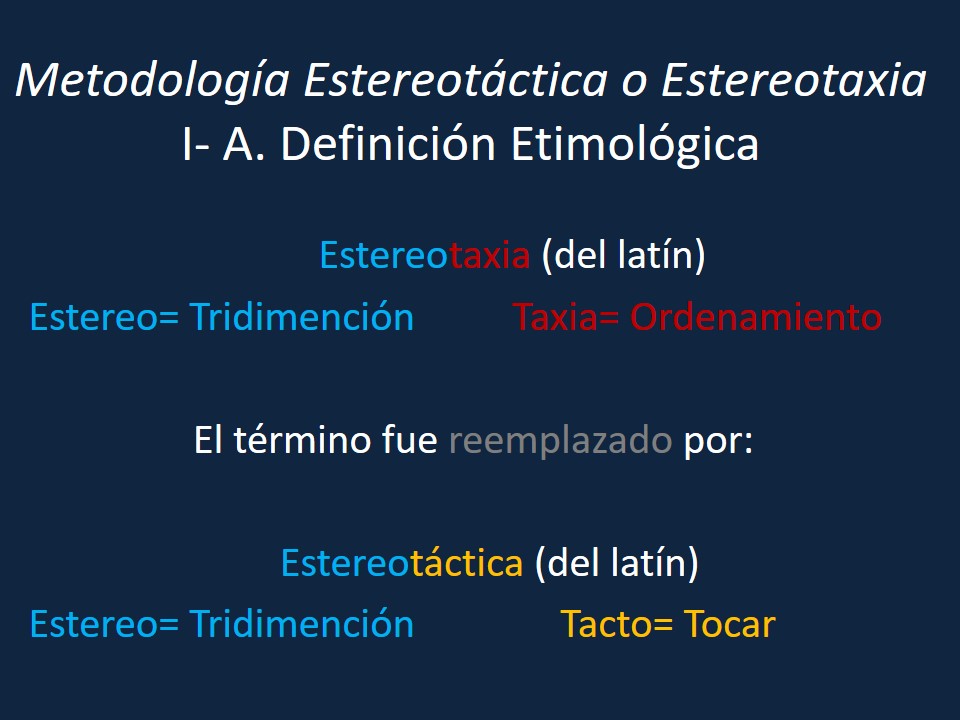

Metodología Estereotáctica o Estereotaxia